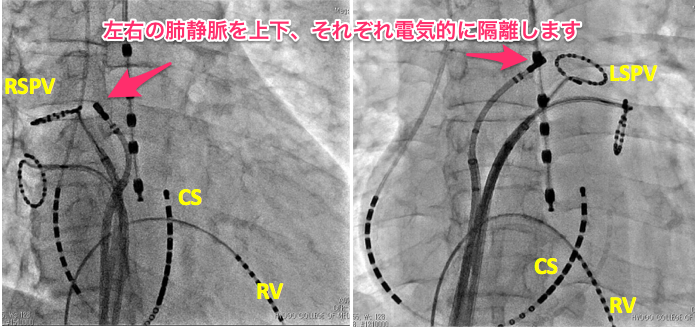

アブレーション Of 兵庫医科大学 循環器内科 冠疾患科